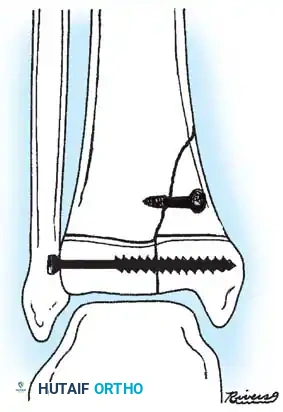

Fig. 33-175: Fixation of a tongue-type Salter-Harris III fracture utilizing cancellous screws.

5. Fixation:

* For vertical fracture components, insert transverse guide pins.

* In older children and adolescents nearing skeletal maturity, utilize 4.0mm or 4.5mm partially threaded cancellous bone screws to achieve interfragmentary compression.

* In younger children with significant remaining growth potential, utilize smooth Kirschner wires (K-wires) placed transversely or horizontally to minimize the risk of physeal arrest.

Placement of transverse fixation pins.

Final construct utilizing cancellous screws for rigid fixation.